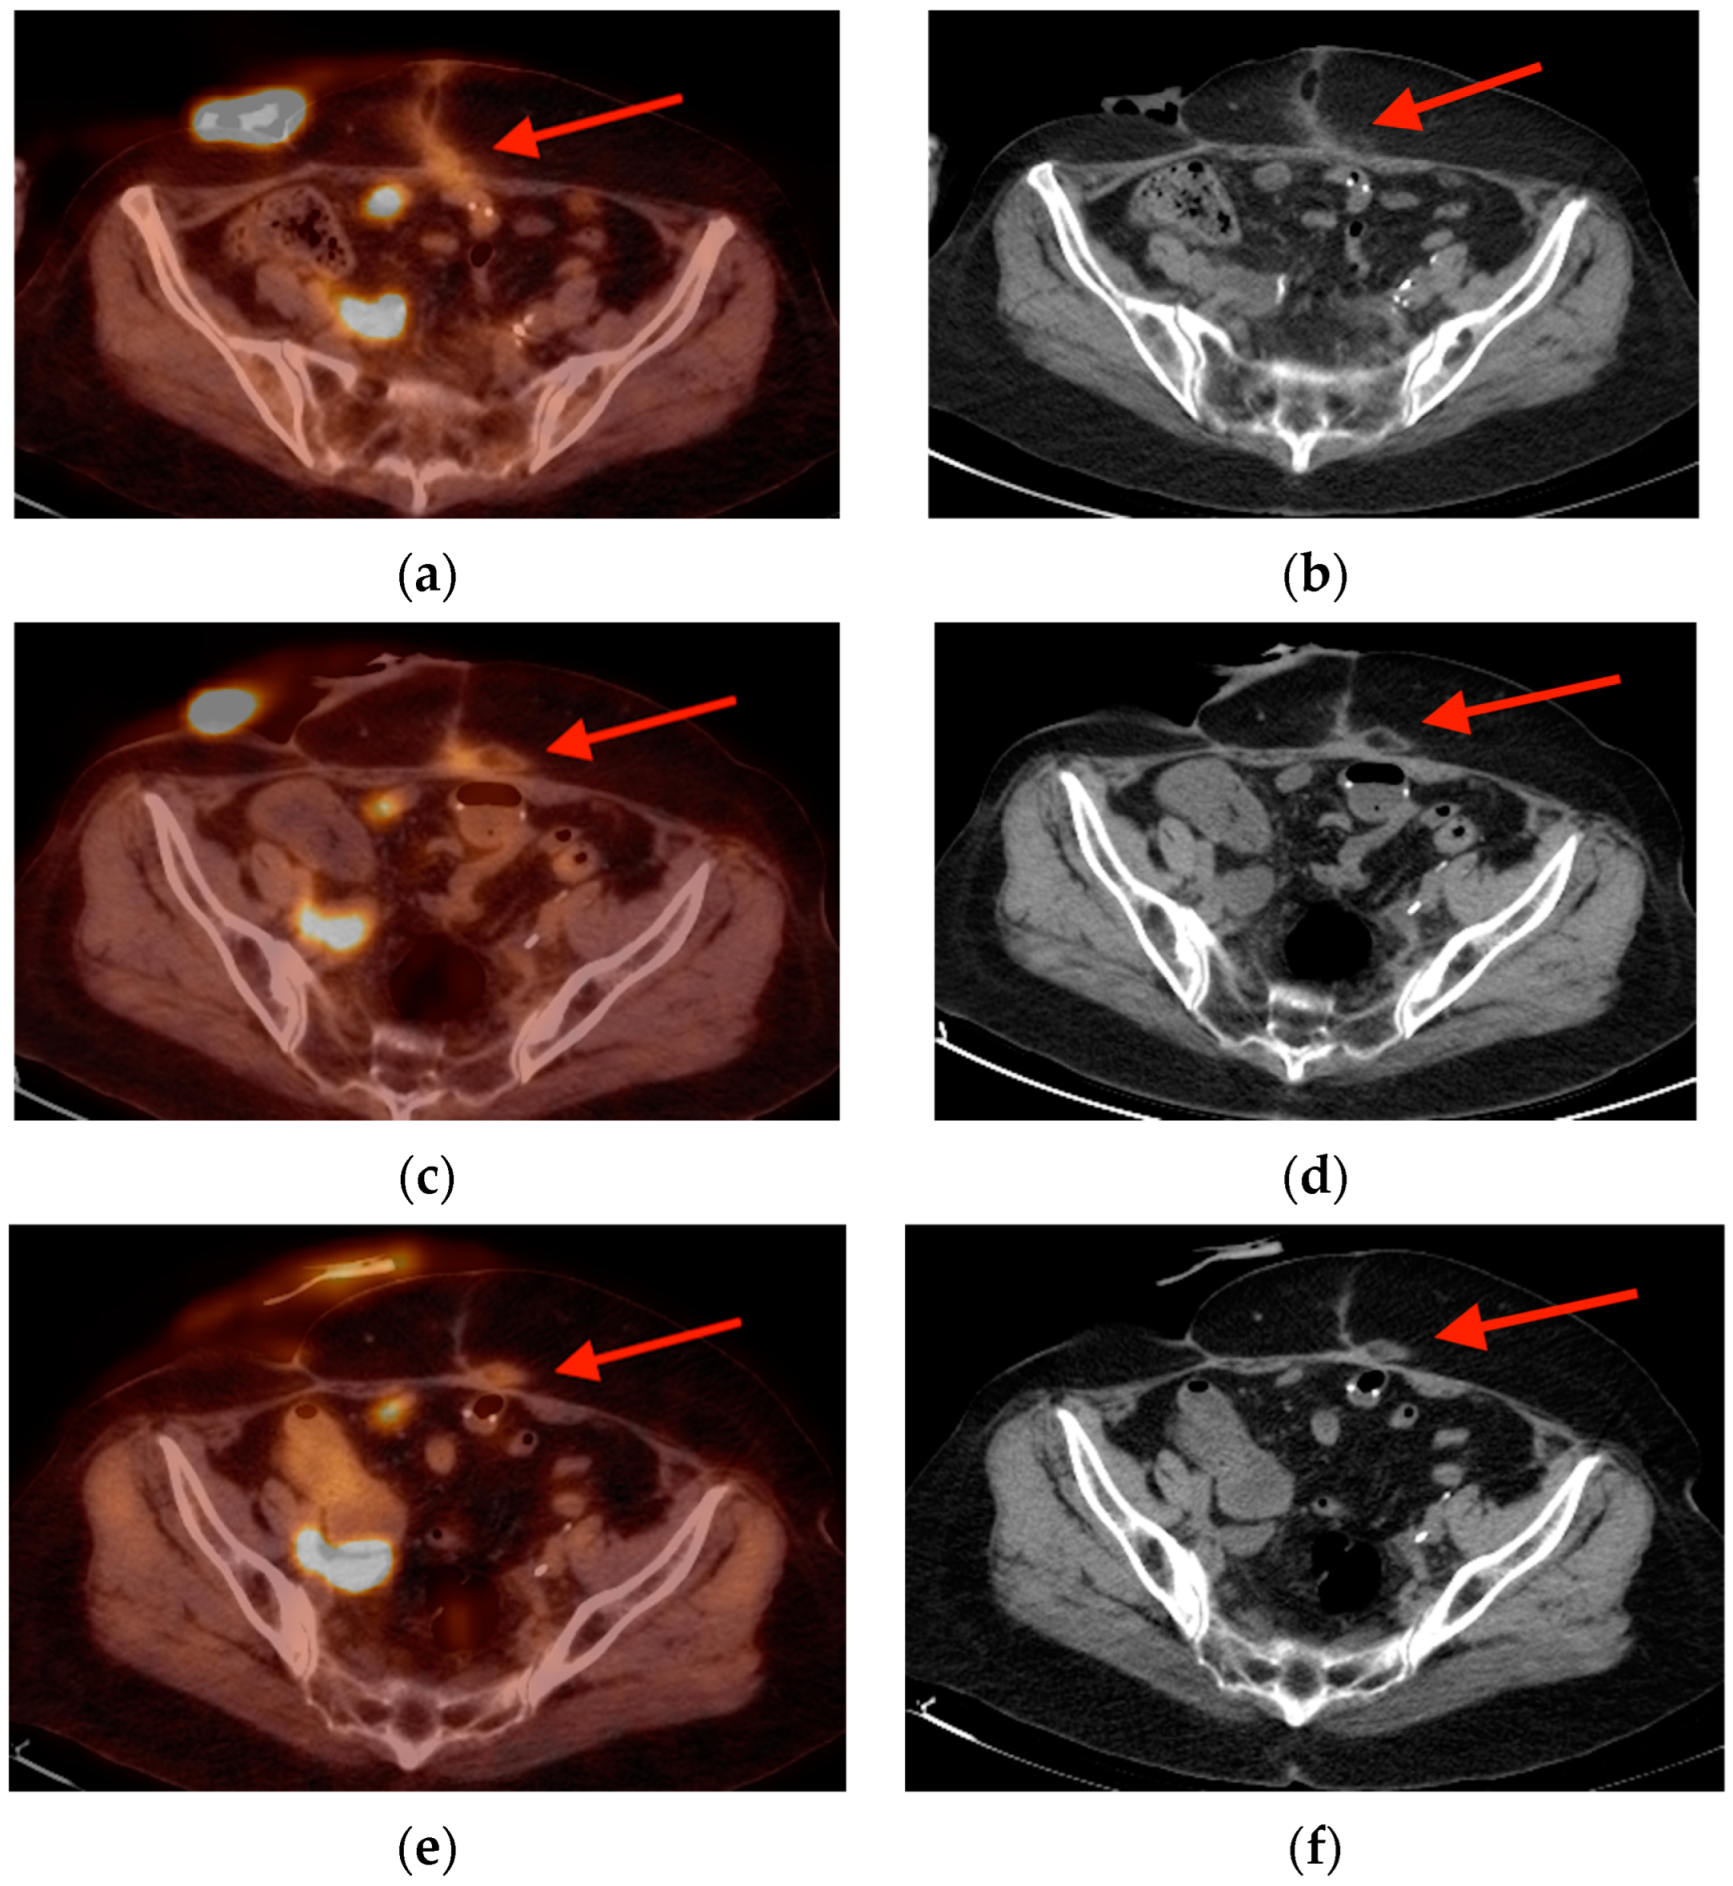

2.6. Paget’s Disease

- Ralston, S.H. Clinical practice. Paget’s disease of bone. N. Engl. J. Med. 2013, 368, 644–650. [Google Scholar] [CrossRef]

- Miller, S.W.; Castronovo, F.P., Jr.; Pendergrass, H.P.; Potsaid, M.S. Technetium 99m labeled diphosphonate bone scanning in Paget’s disease. Am. J. Roentgenol. Radium Ther. Nucl. Med. 1974, 121, 177–183. [Google Scholar] [CrossRef] [PubMed][Green Version]

- Park, E.T.; Kim, S.E. Radiography, Bone Scan, and F-18 FDG PET/CT Imaging Findings in a Patient with Paget’s Disease. Nucl. Med. Mol. Imaging 2010, 44, 87–89. [Google Scholar] [CrossRef] [PubMed][Green Version]

- Sasikumar, A.; Joy, A.; Nanabala, R.; Pillai, M.R.A.; Hari, T.A. 68Ga-PSMA PET/CT False-Positive Tracer Uptake in Paget Disease. Clin. Nucl. Med. 2016, 41, e454–e455. [Google Scholar] [CrossRef]